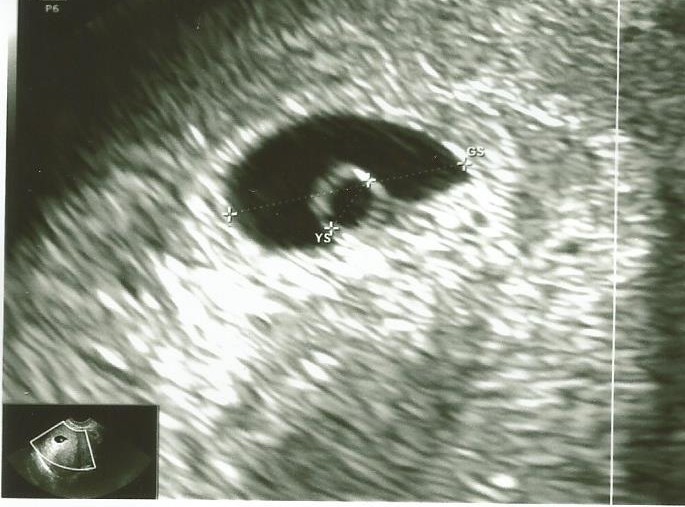

Tu u mnie z OM 6+4 ale tez pecherzyka nie zmierzono ale może sobie porównasz

• E8F7910E-B0A3-4735-BF4D-90B353FC592E.jpeg

E8F7910E-B0A3-4735-BF4D-90B353FC592E.jpeg

119,7 KB · Wyświetleń: 111